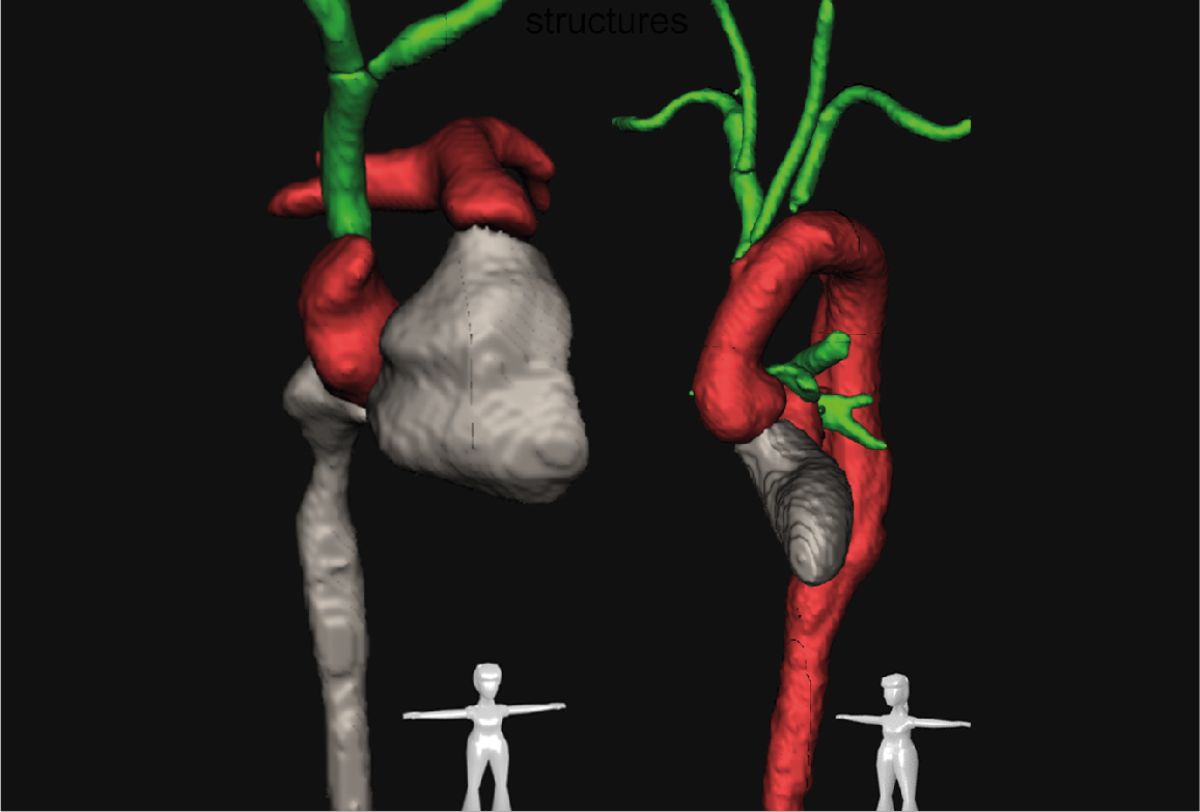

Unsere Radiolog*innen prüfen und nutzen sie nun schon seit Jahren: die künstliche Intelligenz. KI-unterstützt erkennt und analysiert eine von unserern Wissenschaftlern entwickelte Software vollautomatisch anatomische Strukturen in Computertomografien, so etwa diesen Aortenbogen.